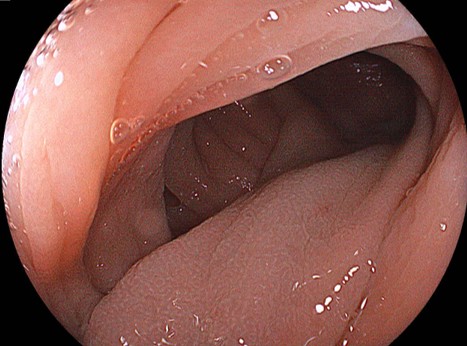

スネアリングするための、適切な場を設定されました。あとはスネアリングするだけです。

エンドカットモードで、短時間で切離することにより切除後潰瘍底に、凝固波による白濁が殆どありません。このように切離すると理論上の後出血のリスクは低くなります。